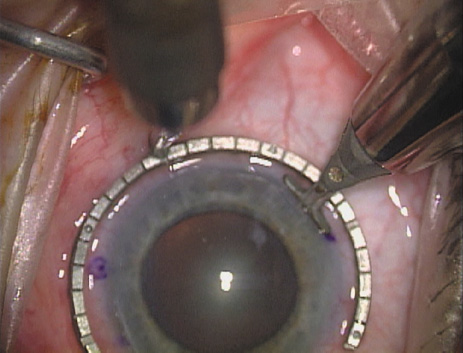

The extent of arc to be incised may be demarcated in several different ways. Our preferred method makes use of a modified Fine-Thornton fixation ring (Nichamin Fixation Ring and Gauge; Mastel Precision, Storz, Rhein Medical). This instrument serves to fixate and position the globe in order to optimize incision placement, as well as to delineate the extent of arc to be incised. One visually extrapolates from the limbus to marks on the surface of the ring. Each incremental mark is 10 degrees apart, and bold hash marks (180 degrees) opposite to each other serve to align and center the incision over the steep meridian. This approach obviates the need to ink and physically mark the cornea. If one desires, particularly when first gaining experience with LRIs, a two-cut RK marker may be used to place ink marks upon the cornea to show the exact extent of arc that is to be incised, in conjunction with the fixation ring/gauge (Fig. 4). Alternatively, various press-on markers are available, such as those made by Rhein Medical (Dell-Nichamin Marker, Nichamin-Kershner Marker, or the Ruminson Marker) (Fig. 5). ASICO and other instrument companies offer a full line of dedicated markers, rings, and blades for performing LRIs.

Fig. 4. The Nichamin Fixation Ring and Gauge serves to both fixate the globe and delineate the extent of arc to be incised; a two-cut radial marker may be used to mark the extent of arc to be incised, and the Mastel Nichamin Force AK Diamond Blade with preset depth of 600 microns.